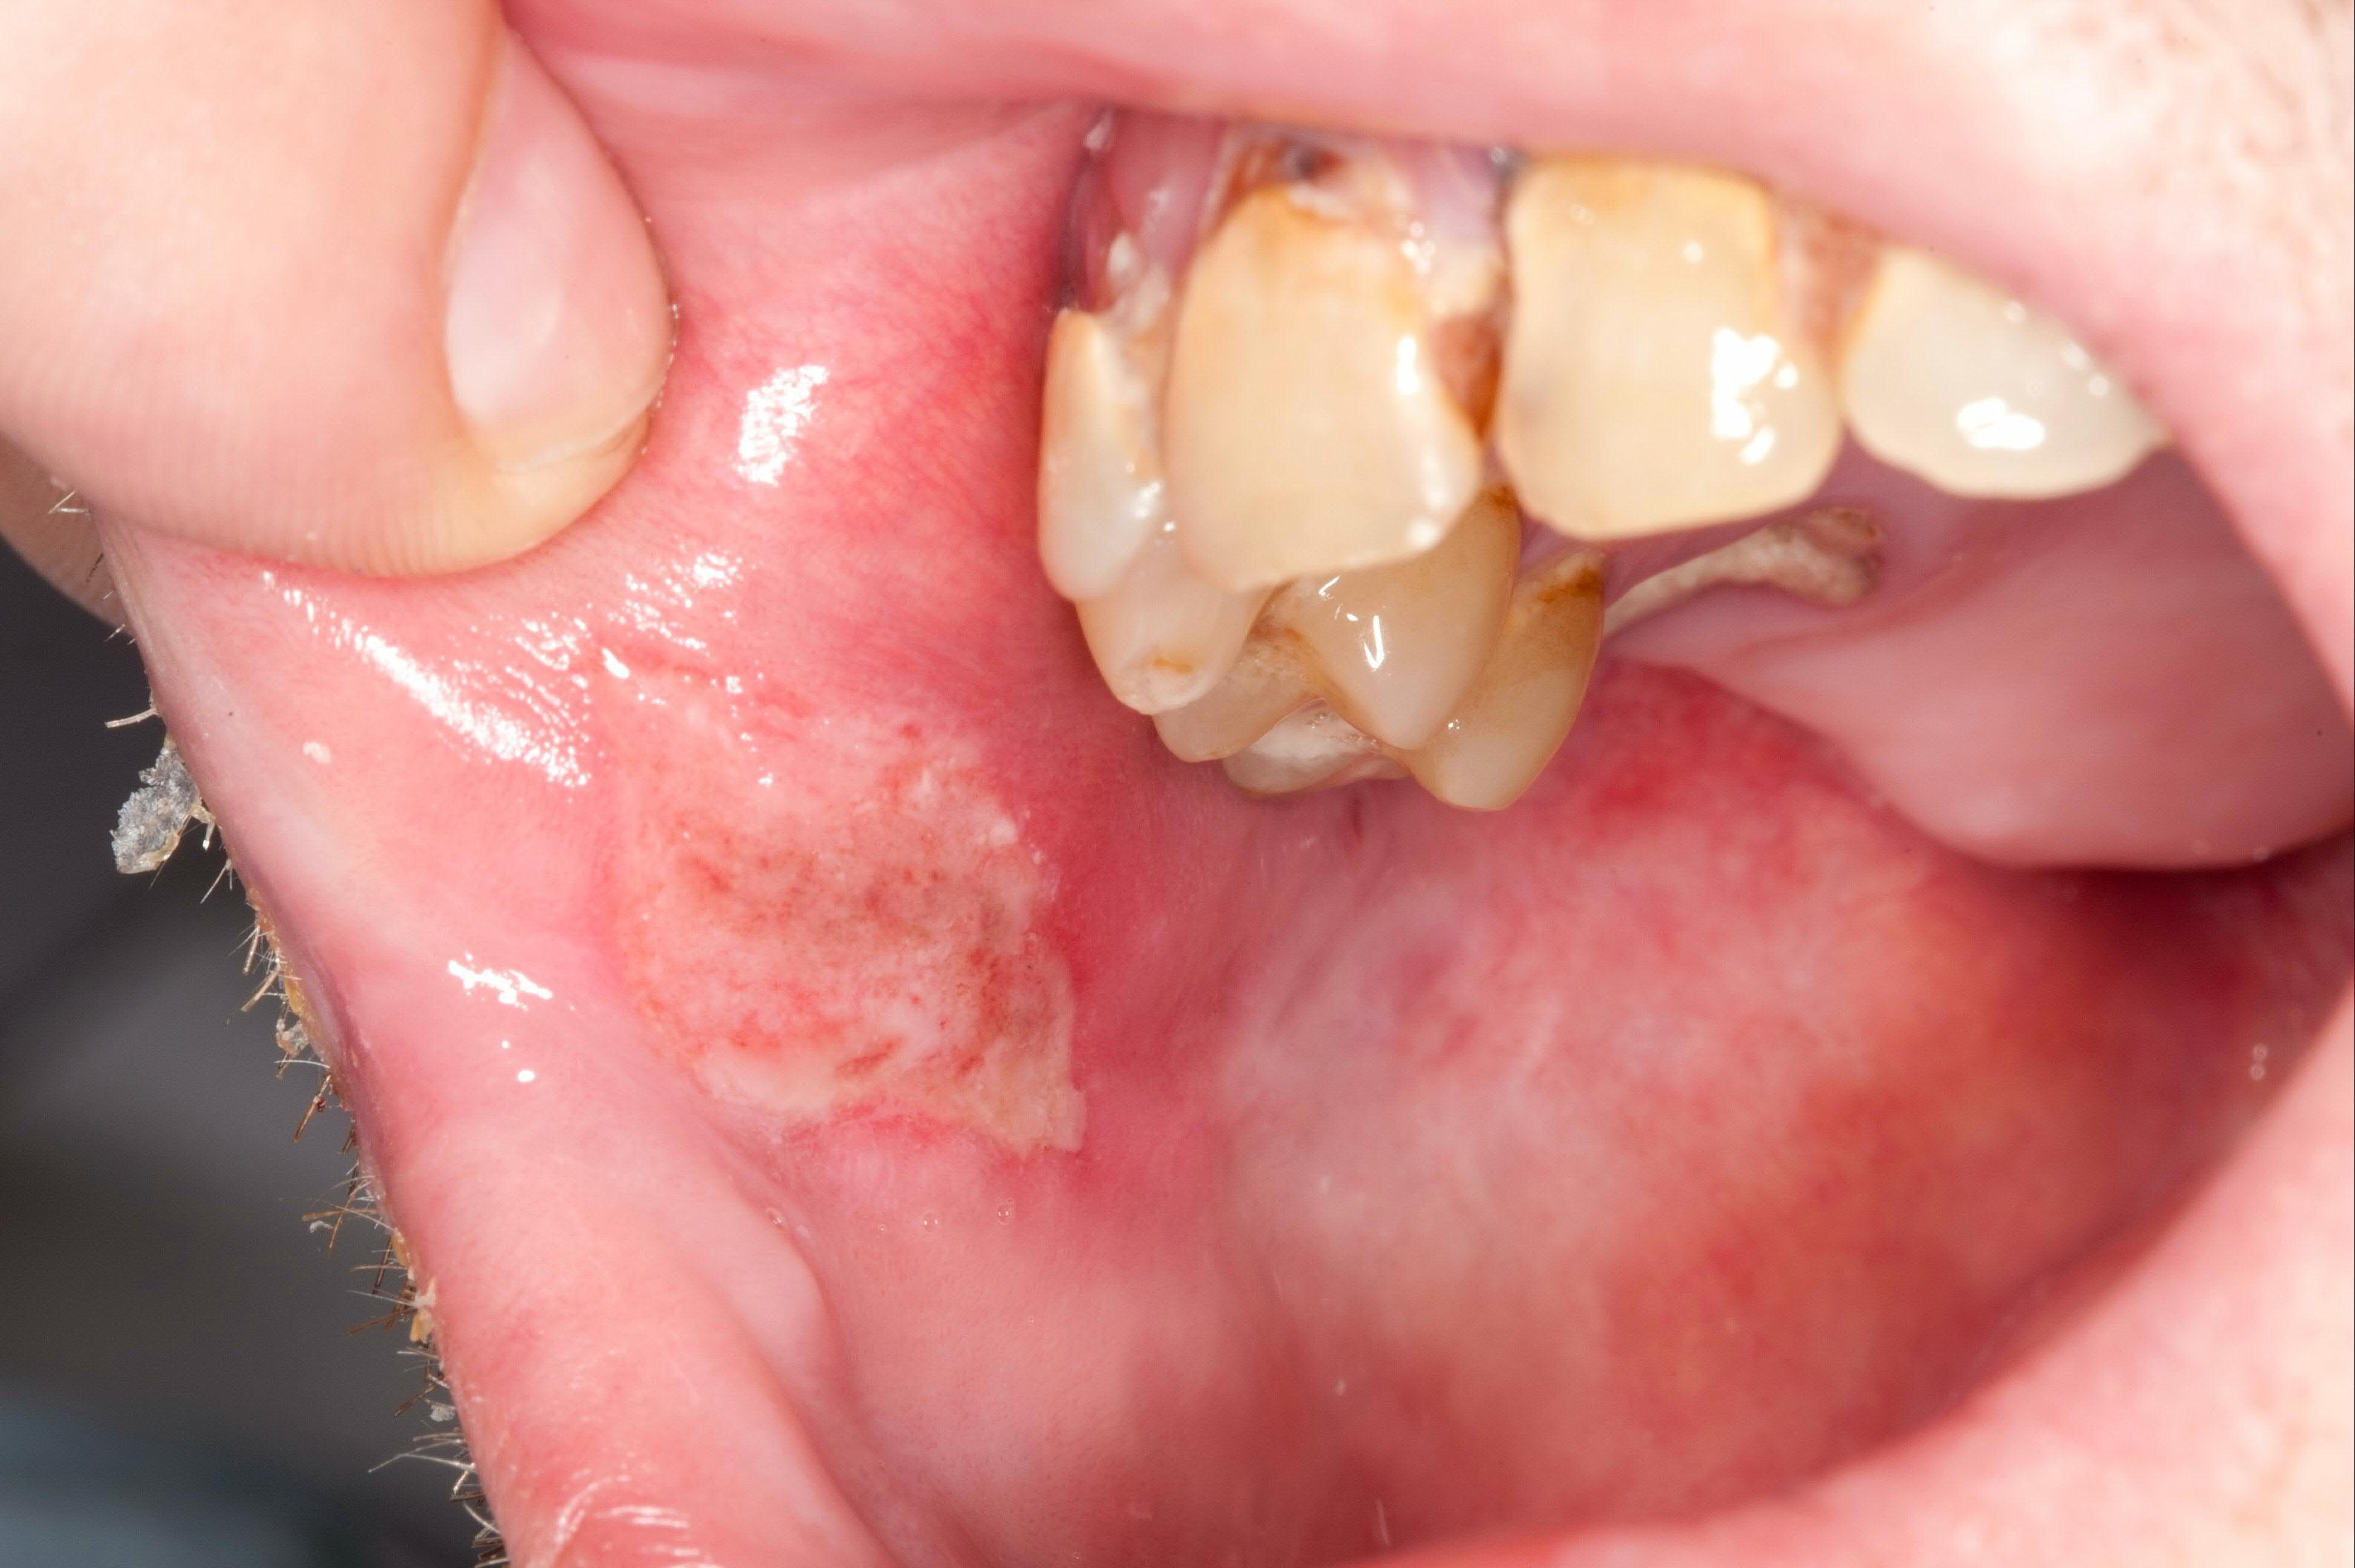

35 yo woman w/ multiple painful oral ulcers, hx anterior uveitis, genital lesions, scattered hyperpigmented lesions, and tender, indurated areas on legs.

dx? what is the image of?

behcet disease

pathergy → exaggerated ulcerating skin response following minor inuries (eg needlestick)

35 yo woman w/ multiple painful oral ulcers (pic), hx anterior uveitis, genital lesions, scattered hyperpigmented lesions, and tender, indurated areas on legs.

dx?